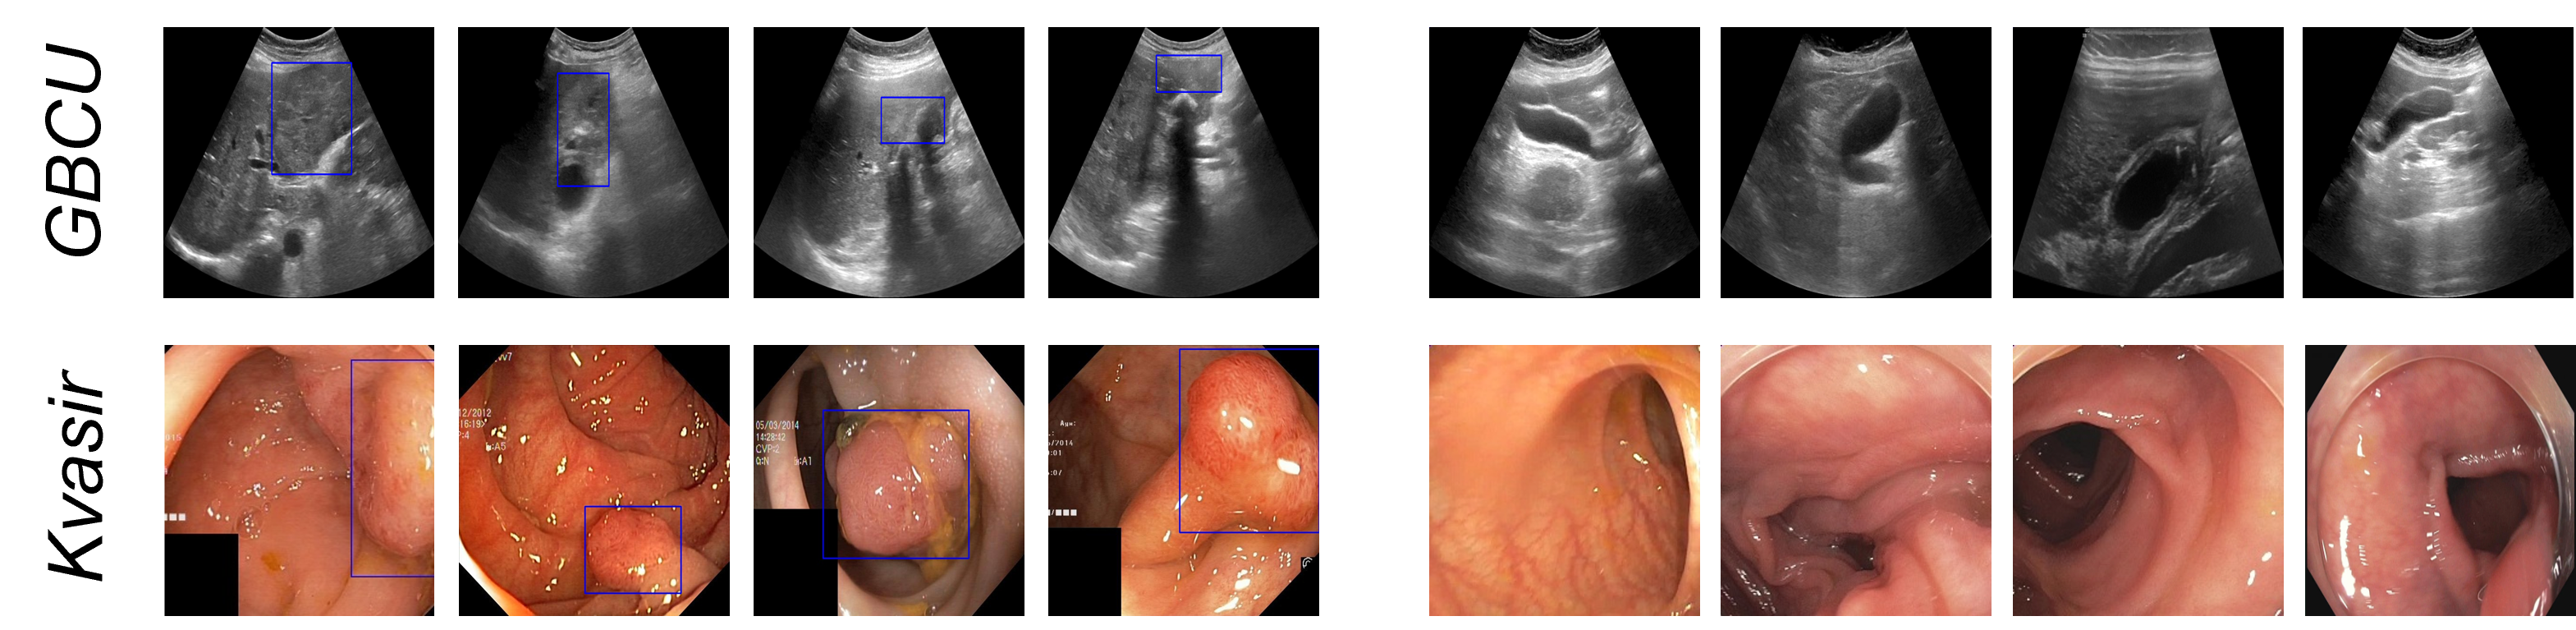

Refer to caption

Figure 2: Samples from the GBCU [3] and Kvasir-SEG [17] datasets. Four images from each of the disease and non-disease classes are shown on the left and right, respectively. Disease locations are shown by drawing bounding boxes.

Gallbladder Cancer Detection in Ultrasound Images: We use the public GBC US dataset [3] consisting of 1255 image samples from 218 patients. The dataset contains 990 non-malignant (171 patients) and 265 malignant (47 patients) GB images (see Fig. 2 for some sample images). The dataset contains image labels as well as bounding box annotations showing the malignant regions. Note that, we use only the image labels for training. We report results on 5-fold cross-validation. We did the cross-validation splits at the patient level, and all images of any patient appeared either in the train or validation split.

Polyp Detection in Colonoscopy Images: We use the publicly available Kvasir-SEG [17] dataset consisting of 1000 white light colonoscopy images showing polyps (c.f. Fig. 2). Since Kvasir-SEG does not contain any control images, we add 600 non-polyp images randomly sampled from the PolypGen [1] dataset. Since the patient information is not available with the data, we use random stratified splitting for 5-fold cross-validation.